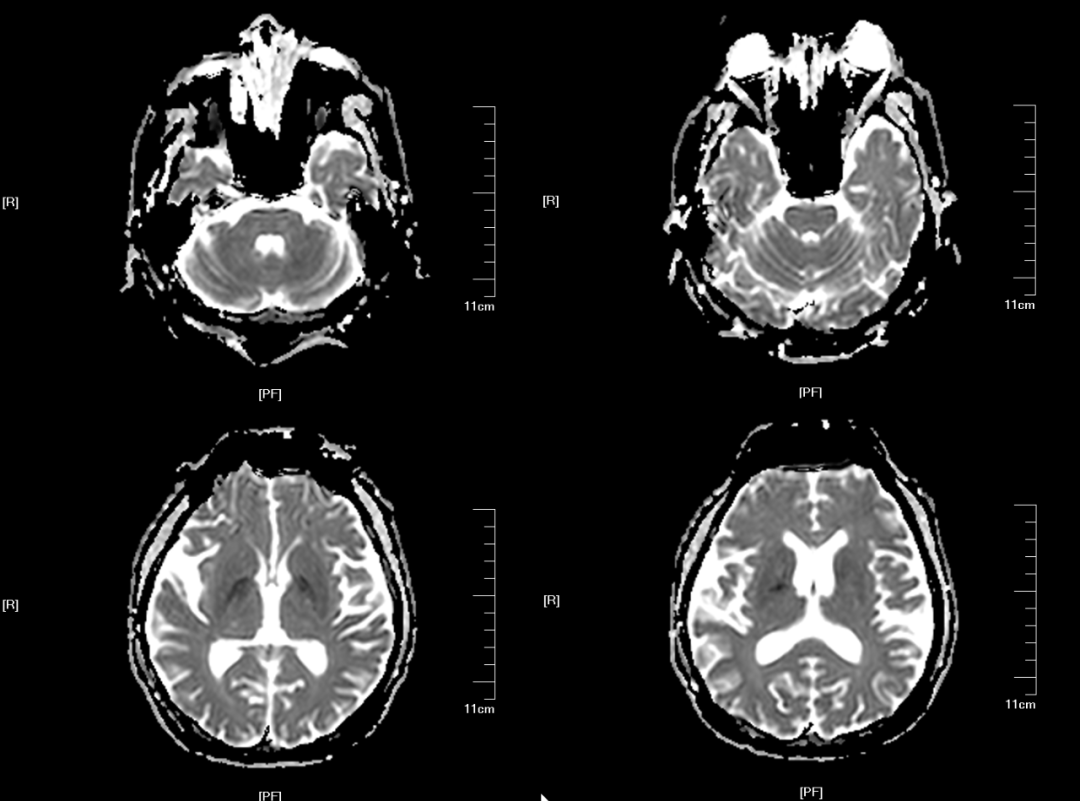

Case1:女,66 岁,3 个月前因间断意识不清就诊于我院,明确诊断为「原发性胆汁性肝硬化 失代偿期、肝性脑病」,给予保肝、降黄、抗感染、对症支持治疗后好转出院。近 2 周内患者出现嗜睡,间断意识不清。血钠 137 mmol/L。

Case2:男,60 岁,发现乙肝病原学阳性 25 年,黑便 1 天,伴有头晕、恶心、乏力,血钠 135.8 mmol/L。

Case3:男,56 岁,因「阵发性耳鸣 15 天,头晕、视物模糊 6.5 天。入院前 15 天出现阵发性耳鸣,性质如鸣笛音,持续约数秒,发作频率大约 1-2 次/天,入院前 6.5 天无明显诱因出现头晕、视物模糊,表现为头重脚轻感,走路不稳,无天旋地转感。既往:2 个月前出现过 3 次头晕,当时伴有视物旋转感。饮酒 30 余年,以前 7-8 两/天。